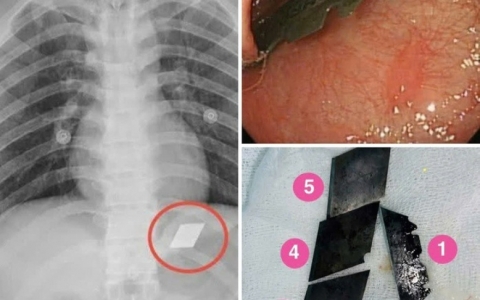

Ống thông truyền hóa chất bị đứt, trôi vào tim khiến người phụ nữ nguy kịch

Sự cố hy hữu khi ống thông truyền hóa chất bị đứt và trôi sâu vào tim khiến người phụ nữ đối diện các biến chứng nguy hiểm tính mạng.